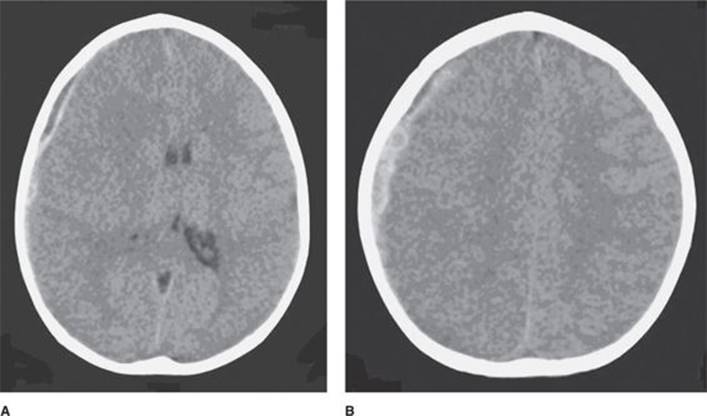

Nonaccidental trauma in infants and young children may result in the constellation of subdural hematoma, subarachnoid hemorrhage, and localized or diffuse brain edema (Fig. 23-3). Retinal hemorrhages, rib fractures, long-bone fractures, and external signs of injury may also be present. Common symptoms of nonaccidental traumatic brain injury in infants may include lethargy, vomiting, irritability, seizures, apnea, and severe alteration in consciousness.9,10

FIGURE 23-3. Right-sided subdural hematoma with associated midline shift and right hemispheric edema in an infant with nonaccidental head trauma.